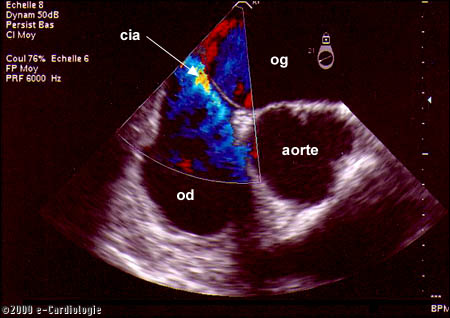

Description

dune communication entre loreillette gauche et loreillette

droite lors de la réalisation dune échographie du

cur par voie trans-oesophagienne. La couleur bleue-verte correspond

à laccélération du sang entre les deux cavités.

cia: communication inter-auriculaire,

vg: ventricule gauche, vd: ventricule droit,

og: oreillette gauche, od: oreillette droite.